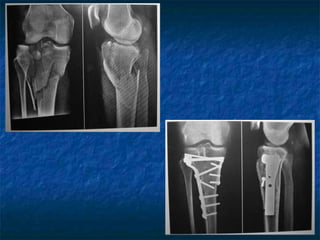

Tratamento Cirúrgico

 Lesões tipo IV: acesso anteromedial, traumas de

baixa energia pode ser tratado com canulados,

de alta energia usar placas de apóio. Fragmento

predominantemente posterior – pode ser

necessário acesso póstero-medial.

 Lesões do tipo V e VI: redução indireta por meio

de distrator, fixação e uso de enxertos. Pode se

combinar duas placas, ou fixação interna e

externa, ou usar fixador externo híbridos.